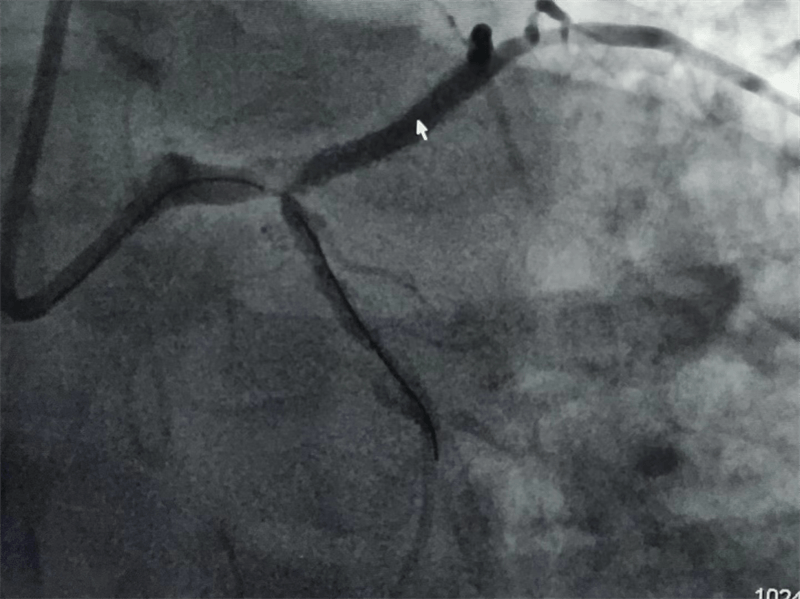

63歲的張大伯因嚴(yán)重心絞痛住院,心電圖可見明顯明顯心肌缺血。主治醫(yī)師黃永濤向患者講明病情后,征得患者和家屬同意,行冠脈造影檢查。真是不做不知道,一做嚇一跳。

冠脈造影結(jié)果提示:左主干末端及前降支開口處99%狹窄,回旋支開口處80-90%狹窄,中段支架內(nèi)100%閉塞??吹皆煊敖Y(jié)果時(shí),在場(chǎng)醫(yī)護(hù)人員無(wú)不驚出一身冷汗:左主干病變“細(xì)”如發(fā)絲——生死一線牽!患者拒絕搭橋手術(shù),所以選擇介入處理該病變。